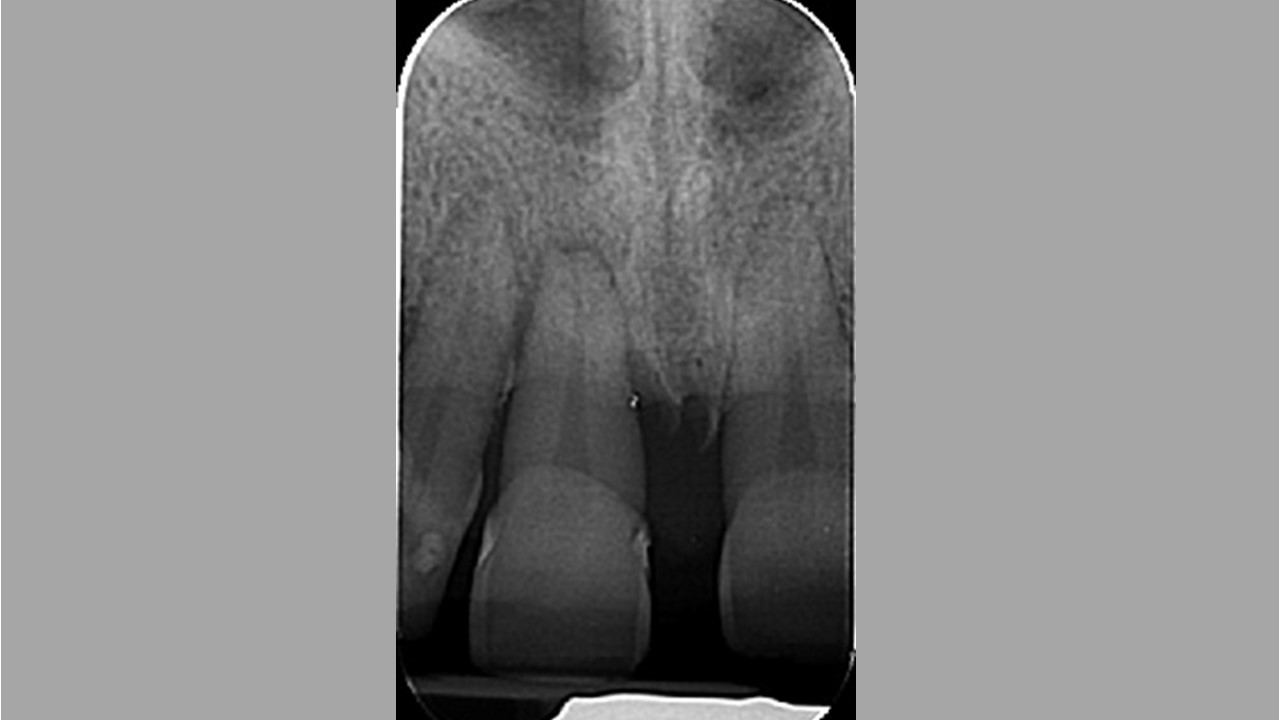

Immediate implant placement in the maxilla with contour GBR - Dr. K. Loukas

The patient presented with a terminal fracture of the crown tooth number 12